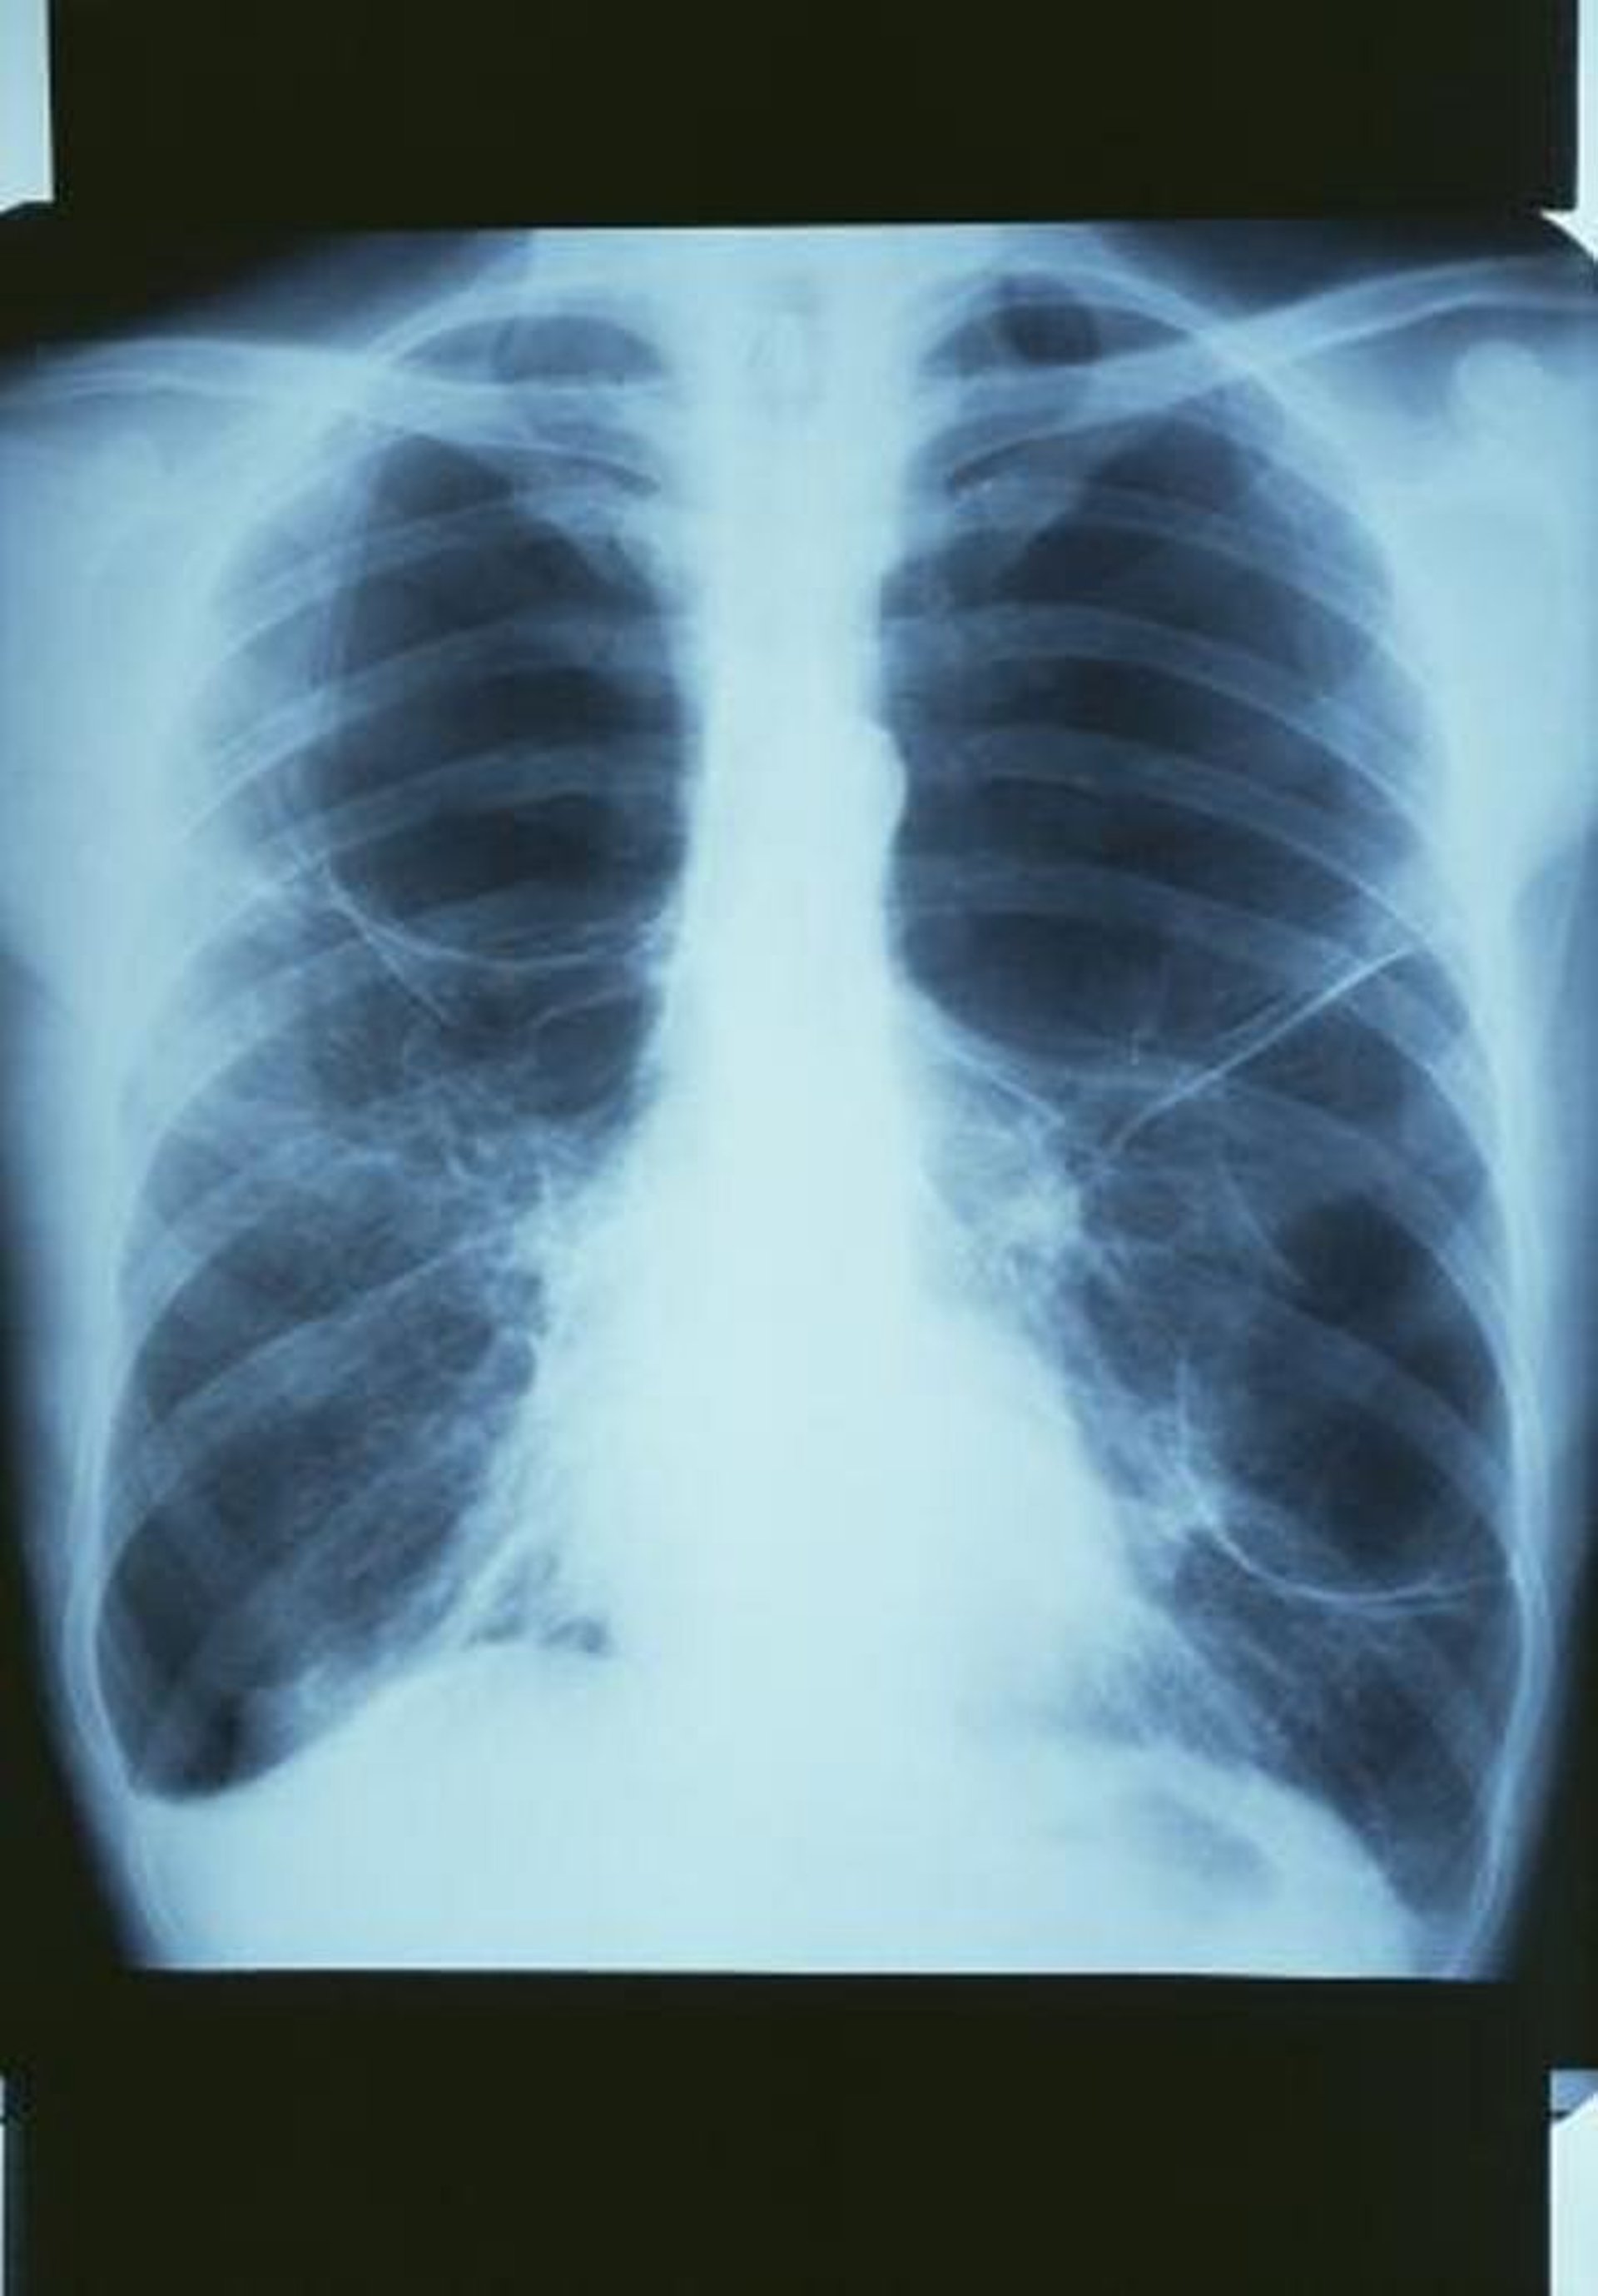

COPD mit Bullae

Diese Röntgenaufnahme des Thorax zeigt eine große Bulla in der oberen rechten Lunge und 2 große Bullae in der linken Lunge.

GJLP/CNRI/SCIENCE PHOTO LIBRARY